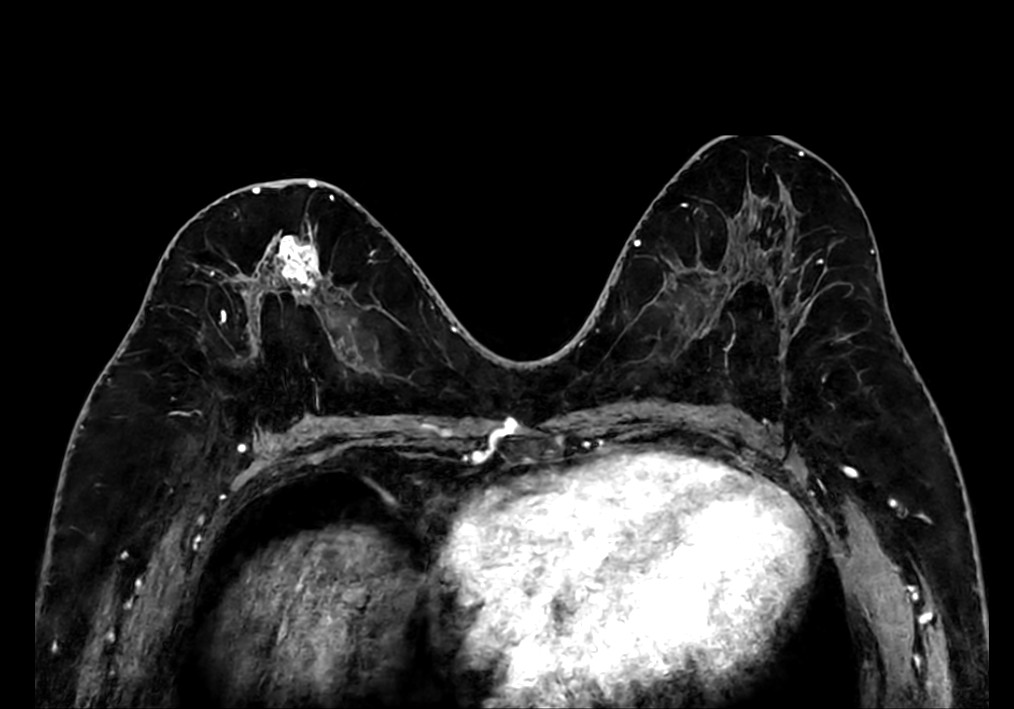

Axial T1w mDIXON FFE (Water only)